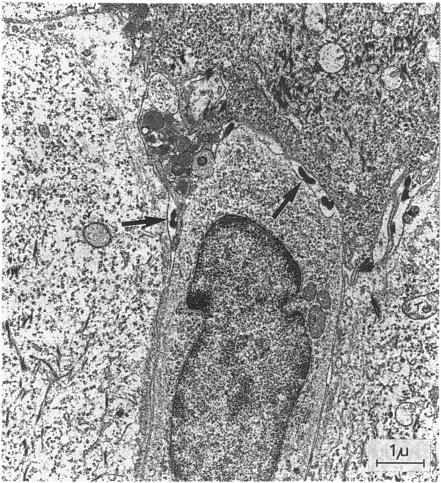

Biopsy material originating from skin lesions in ten young children suffering from early infectious yaws in Indonesia, and rabbit testicular tissue inoculated with T pertenue. Human skin as well as rabbit testicular tissue was examined by means of conventional electron microscopy.

In human skin, treponemes were found in interepidermal spaces in 5 out of 10 specimens. In two of five positive specimens, treponemes were also seen in the dermis. In one out of five specimens from rabbit testicular tissue a profusion of treponemes was found lying in the interstitial myxomatous tissue. Microorganisms showed no adhesion to fibroblasts.

This ultrastructural study of T pertenue demonstrated the scarcity and focal distribution of treponemes in tissue and did not reveal any morphological differences from the Gauthier strain of T pertenue. No differences from the ultrastructure of T pallidum were observed either.

取自印度尼西亚10名患有早期感染性雅司病的幼儿皮肤病变的活检材料,以及接种了品他密螺旋体的兔睾丸组织。采用传统电子显微镜检查人皮肤和兔睾丸组织。

在人皮肤中,10个标本中有5个在表皮间隙发现了密螺旋体。在5个阳性标本中的2个中,真皮中也可见密螺旋体。在兔睾丸组织的5个标本中的1个中,在间质黏液瘤样组织中发现大量密螺旋体。微生物未显示与成纤维细胞的黏附。

本品他密螺旋体的超微结构研究表明,密螺旋体在组织中的数量稀少且呈局灶性分布,与品他密螺旋体的高蒂埃菌株在形态上没有差异。也未观察到与梅毒螺旋体超微结构的差异。